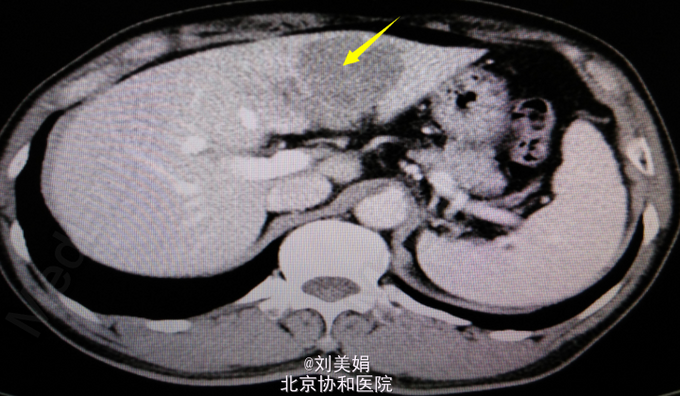

患者 男 58岁 主 诉:乙肝20余年,发现肝脏占位1月余 现病史:患者乙肝病史20余年,间断口服保肝药物,并定期复查肝功,肝功能目前可。每年常规行腹部B超检查,均未见明显异常。1月前体检,行腹部CT发现肝脏占位。患者无畏寒发热、腹痛腹胀、恶心呕吐、皮肤黄染等。于2015年7月10日我院门诊就诊,行腹部增强CT+三维重建示:肝左叶见不规则状稍低密度影,最大截面约为6.0cm×4.6cm,增强后动脉期可见明显强化,门脉期及延迟期强化程度减低,呈“快进快出”强化,肝左动脉分支参与病变供血,门静脉左支局部明显变细,肝门区、小网膜囊内、腹膜后多发淋巴结,部分增大。考虑:肝左内叶占位,考虑恶性病变可能性大;肝左动脉分支参与病变供血,门静脉左支局部明显变细,局部受累可能;肝门区、小网膜囊内、腹膜后多发淋巴结,部分增大。肝肾功:AST 67U/L,LD 254U/L,TBil 13.2μmol/L,DBil 4.5μmol/L,Cr(E) 79μmol/L,ALT 45U/L,Alb 48g/L,GGT 47U/L。

腹部增强CT+三维重建:肝左内叶占位,考虑恶性病变可能性大;肝左动脉分支参与病变供血,门静脉左支局部明显变细,局部受累可能;肝门区、小网膜囊内、腹膜后多发淋巴结,部分增大;双肾多发结石;左肾小囊肿;腹主动脉及其分支动脉粥样硬化性改变;胸腰椎骨质增生。